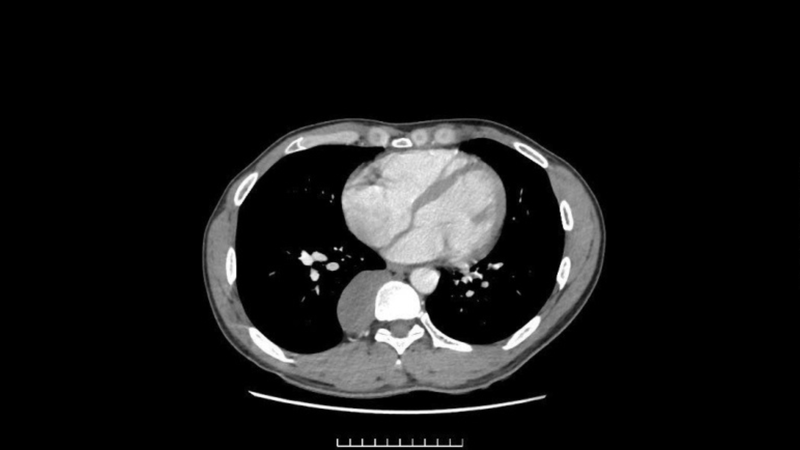

Khi thực hiện chụp CT và MRI lồng ngực, bác sĩ phát hiện một khối u kích thước khoảng 33 x 90 x 32 mm kéo dài từ D7 đến D11, mật độ chắc, nằm sát cột sống và có dấu hiệu xâm lấn màng phổi. Vị trí giải phẫu phức tạp này làm tăng nguy cơ tổn thương: